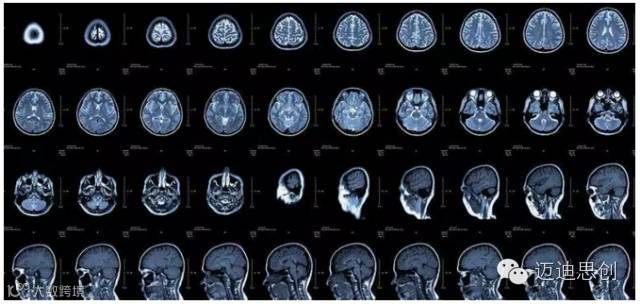

核磁共振:摇一摇再看

核磁共振机使用较强大的磁场,使人体中所有水分子磁场的磁力线方向一致,这时核磁共振机的磁场突然消失,身体中水分子的磁力线方向,突然恢复到原来随意排列的状态。简单说就相当于用手摇一摇,让水分子振动起来,再平静下来,感受一下里面的振动。所以,核磁共振(MRI)也被戏说为是摇摇看的检查。

2、颈椎腰椎——最佳选核磁、次选CT

颈椎病、腰椎间盘突出等椎间盘疾病需要观察椎间盘与相应的神经根,要想更好观察这些软组织,最优选择就是核磁。同样,对于关节、肌肉、脂肪组织检查,核磁也是首选。